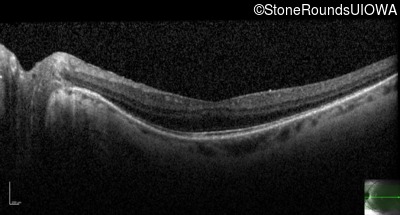

AD Retinitis Pigmentosa (IA1aii)

Age at visit:

53 years

OD

OS

20/16 -2

20/16 -1

OCT Stack

Diagnosis & molecular findings

Disease

Gene

Allele 1 variant(s)

Allele 2 variant(s)

Inheritance mode

AD Retinitis Pigmentosa

SNRNP200

Ser1087Leu TCG>TTG

AD